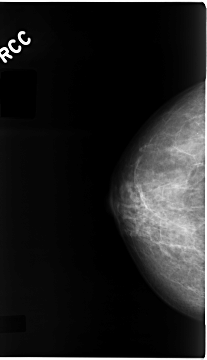

C_0115_1.RIGHT_CC

RIGHT_CC LINES 4672 PIXELS_PER_LINE 2680 BITS_PER_PIXEL 12 RESOLUTION 50 NON_OVERLAY